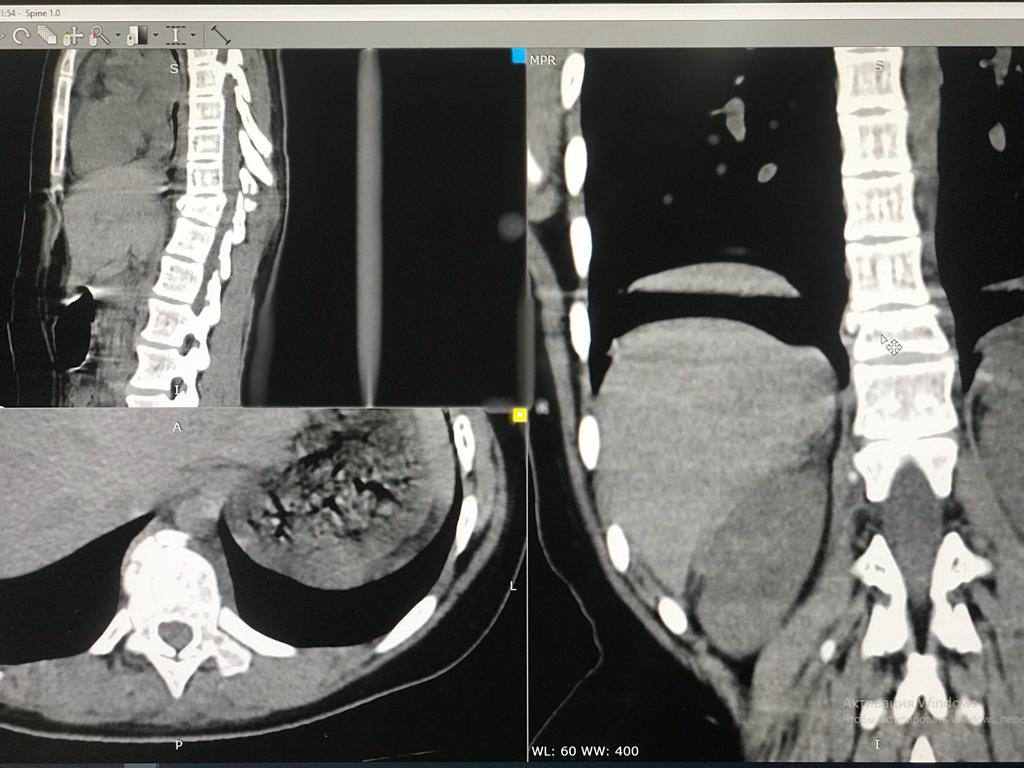

В последних числах апреля подростки катались на качелях. Одна из девочек случайно упала и получила сильнейшую травму. У ребенка диагностировали перелом позвоночника с деформацией и ушибами внутренних органов.

Врачи Центра детской хирургии приняли решение оперировать юную оренбурженку. Уже 4 мая девочке провели операцию, которая длилась три часа, и установили специальную фиксирующую конструкцию. Все вмешательства проводились под полным рентген-контролем.